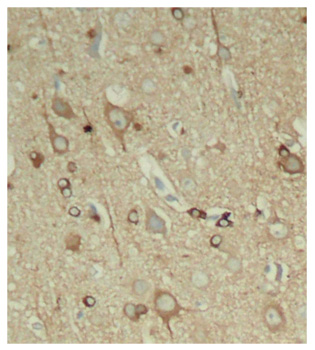

Immunohistochemistry of paraffin-embedded rat hippocampal region tissue from a model with Alzheimer, using Phospho-Tau-S396 antibody. |